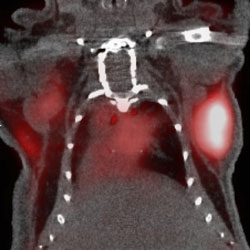

Figure: PET Image Quality Improvement Using Tissue-Dependent, Spatially-Variant Positron Range Correction. Images show a coronal slice of the PET/CT image of a mouse thorax with xenografted neuroendocrine tumors (NET). The CT image is depicted in black and white while the white and red is the resulting PET image for the 68Ga-DOTATOC radiotracer that binds to the somatostatin receptor expressed by the NET (contrast is enhanced for better visualization). (A) Non-PR corrected reconstruction produces a blurrier image with less defined contours plus a background haze that limits the accurate delineation of the tumor (hot area under the right foreleg); (B) PR-corrected image where the haze has disappeared and the tumor can be better delineated; (C) Horizontal profile across the mouse thorax depicting the PET image intensity showing how the PR-correction improves the uptake quantification on every tissue.

PET imaging offers excellent translational possibilities due to its combination of sensitivity and quantitative accuracy. It provides very useful information about tissue and organ function and status, and the type of physiological information provided depends on the specific imaging agent used. The process begins with the injection of a radioactive compound called radiotracer (at a harmless low dose) followed by the detection of the positron-mediated gamma radiation emitted. The positrons travel a certain distance in tissue until they annihilate into the two gamma photons detected by the scanner. This distance or “positron range” (PR) is one of the main sources of PET imaging blurring, but its effect could be remedied to a large extent if accurate estimates of this phenomenon are considered during the image reconstruction process.

Previously proposed methods to remove the PR effect in PET images have proved to be only partially effective because they ignored the boundaries between tissues of different density. The solution proposed in this work models PR effects in the image reconstruction algorithm as 3D anisotropic (spatially-variant) blurring kernels based on the tissue density-dependent radial profile of the annihilation points. This tissue-dependency is extracted from the CT image that is acquired together with the PET. If cleverly implemented, this approach has a small computational cost, it improves significantly the quality of the reconstructed images, rendering material-dependent PR corrected images, and removes edge artifacts frequently seen in clinical and preclinical images.

This advanced algorithm produces better quantification of the lesions of interest, giving activity values closer to the theoretical ones. Regarding mice studies, the quantification of tumor activities improves significantly because it allows a more precise delineation of the different tissue boundaries, among other reasons.